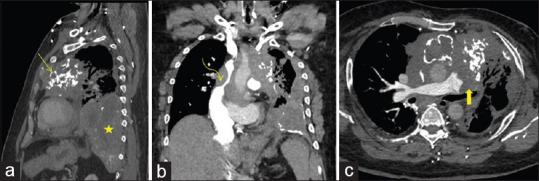

The treatment of malignant superior vena cava syndrome (SVCS) revolves around radiotherapy and chemotherapy to relieve symptoms with surgery being ruled out due to the advanced stage of malignancy. Primary placement of endovascular stent for palliation of malignant SVCS is not commonly reported in the literature. Here, we present two cases of malignant superior vena cava syndrome with successful relief of symptoms after the placement of endo vascular stent.

恶性上腔静脉综合征(SVCS)的治疗主要围绕放疗和化疗以缓解症状,由于恶性肿瘤处于晚期,手术被排除在外。文献中较少报道通过血管内支架置入术来缓解恶性SVCS的症状。在此,我们报告两例恶性上腔静脉综合征患者,在置入血管内支架后症状成功缓解。